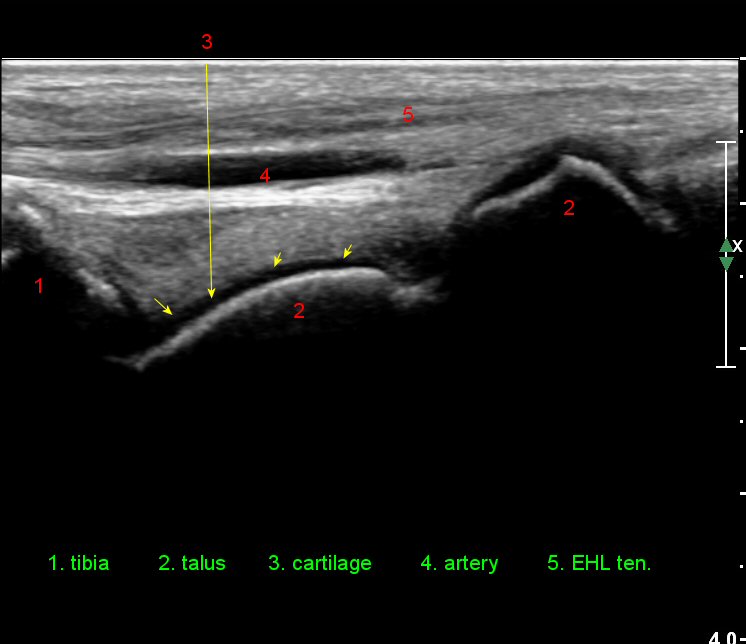

¹ß¸ñ°üÀý ¾ÕÂÊ Á¾´Ü¸é°Ë»ç¿¡¼­ ƯÀÌ ¼Ò°ßÀ» º¸ÀÌÁö ¾ÊÀ¸³ª(»çÁø 1)

ŽÃËÀÚ¸¦ ÀÎÁ¢ÇÑ ºÎÀ§·Î À̵¿ÇÏ´Ï ¼Ò·®ÀÇ °üÀý³» ¼ö¾×Àú·ù°¡ °üÂûµÈ´Ù(»çÁö 2).

¹ß¸ñ°üÀý ¾ÕÂÊ Á¾´Ü¸é°Ë»ç¿¡¼­ °üÀý³» ¼ö¾×Àú·ù°¡ »ç¶óÁö°í(»çÁø 1),

Àü°ÅºñÀδë Á¾´Ü¸é°Ë»ç¿¡¼­  Àú¿¡ÄÚ ºÎÁ¾ÀÌ °¨¼ÒÇϰí ÀδëÀÇ ¿¡ÄÚ°¡ Áõ°¡µÇ¾ú´Ù(»çÁø 2, 3, 4).

Àü°ÅºñÀδë Ⱦ´Ü¸é°Ë»ç¿¡¼­ Àü°Åºñ ÀÎ´ë ¾ÕÂÊ ºÎÀ§ÀÇ °æ¹ÌÇÑ Àú¿¡ÄÚ ºÎÁ¾ÀÌ °üÂûµµ´Ï´Ù(»çÁø 5).